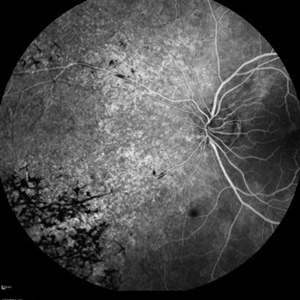

Uveitis of RP variant

FA OD 29-year-old female with serous detachment OD & OS.

Photographer: Stuart Alfred, CRA, OCT-C

Imaging device: 55 degree lens

Condition/keywords: RP variant, serous retinal detachment, uveitis